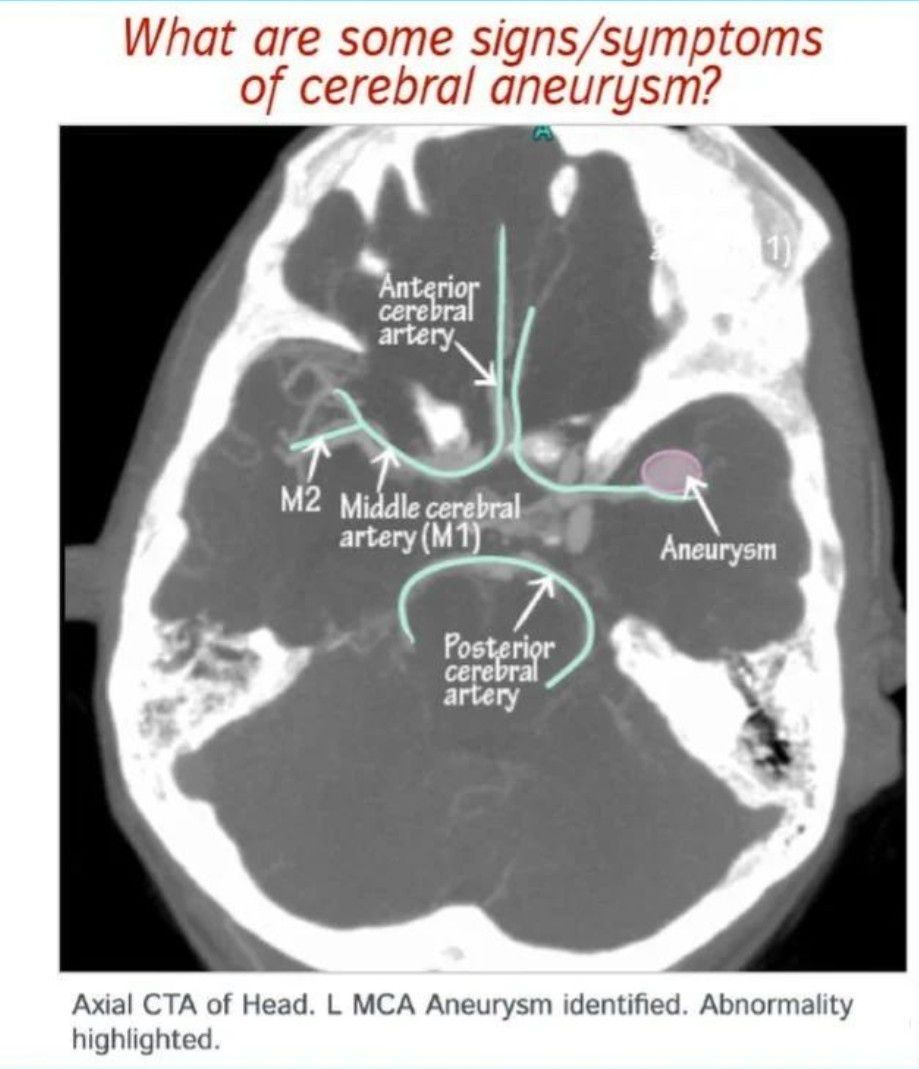

Cerebral Aneurysm

Here is a dive into the basics to refresh your memory